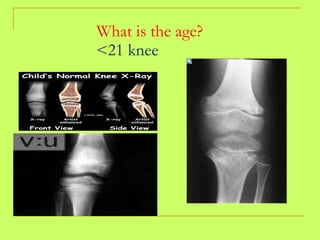

What is the age? <21 knee

What is theage? <21 knee

Ages of legal importance in Egypt: 16years: Age of legal marriage in females-identity card) Metecarpals in females. 18 years: Legal marriage in males ---legal age for consent----- governmental employment---- driving license ----- Full criminal responsibility-------Voting. Metacarpals with their bodies 21 years: Civil rights  X - ray knee

Ages of legalimportance in Egypt: 16years: Age of legal marriage in females-identity card) Metecarpals in females. 18 years: Legal marriage in males ---legal age for consent----- governmental employment---- driving license ----- Full criminal responsibility-------Voting. Metacarpals with their bodies 21 years: Civil rights X - ray knee